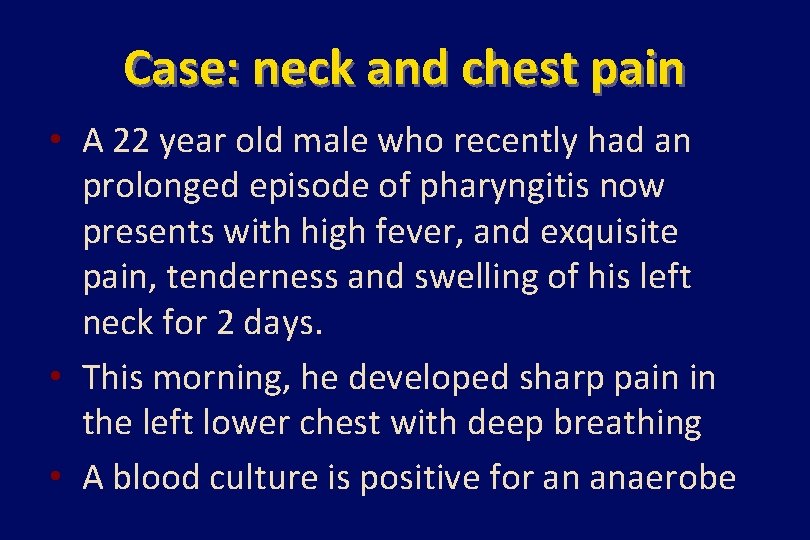

Case: neck and chest pain • A 22 year old male who recently had an prolonged episode of pharyngitis now presents with high fever, and exquisite pain, tenderness and swelling of his left neck for 2 days. • This morning, he developed sharp pain in the left lower chest with deep breathing • A blood culture is positive for an anaerobe